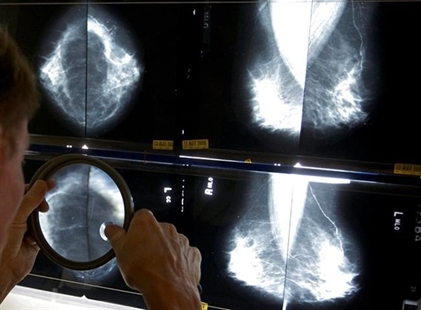

Researchers say a decades-old Canadian study that influenced breast cancer screening policy contained significant flaws…